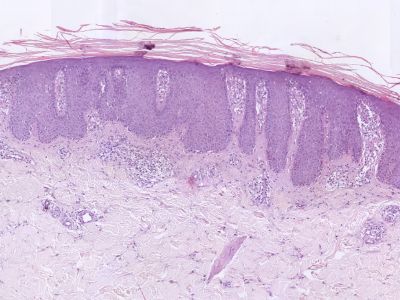

Histologie:

Hyperkeratose, parakeratose (kaarsvetfenomeen), wisselende acanthose, verlengde retelijsten, hoogoplopende dermale papillen (puntbloedinkjes), geen stratum granulosum.

Psoriasis, histologisch beeld Psoriasis, histologisch beeld

Histologie psoriasis Histologie psoriasis

ingescande coupe (zoom) ingescande coupe (zoom)